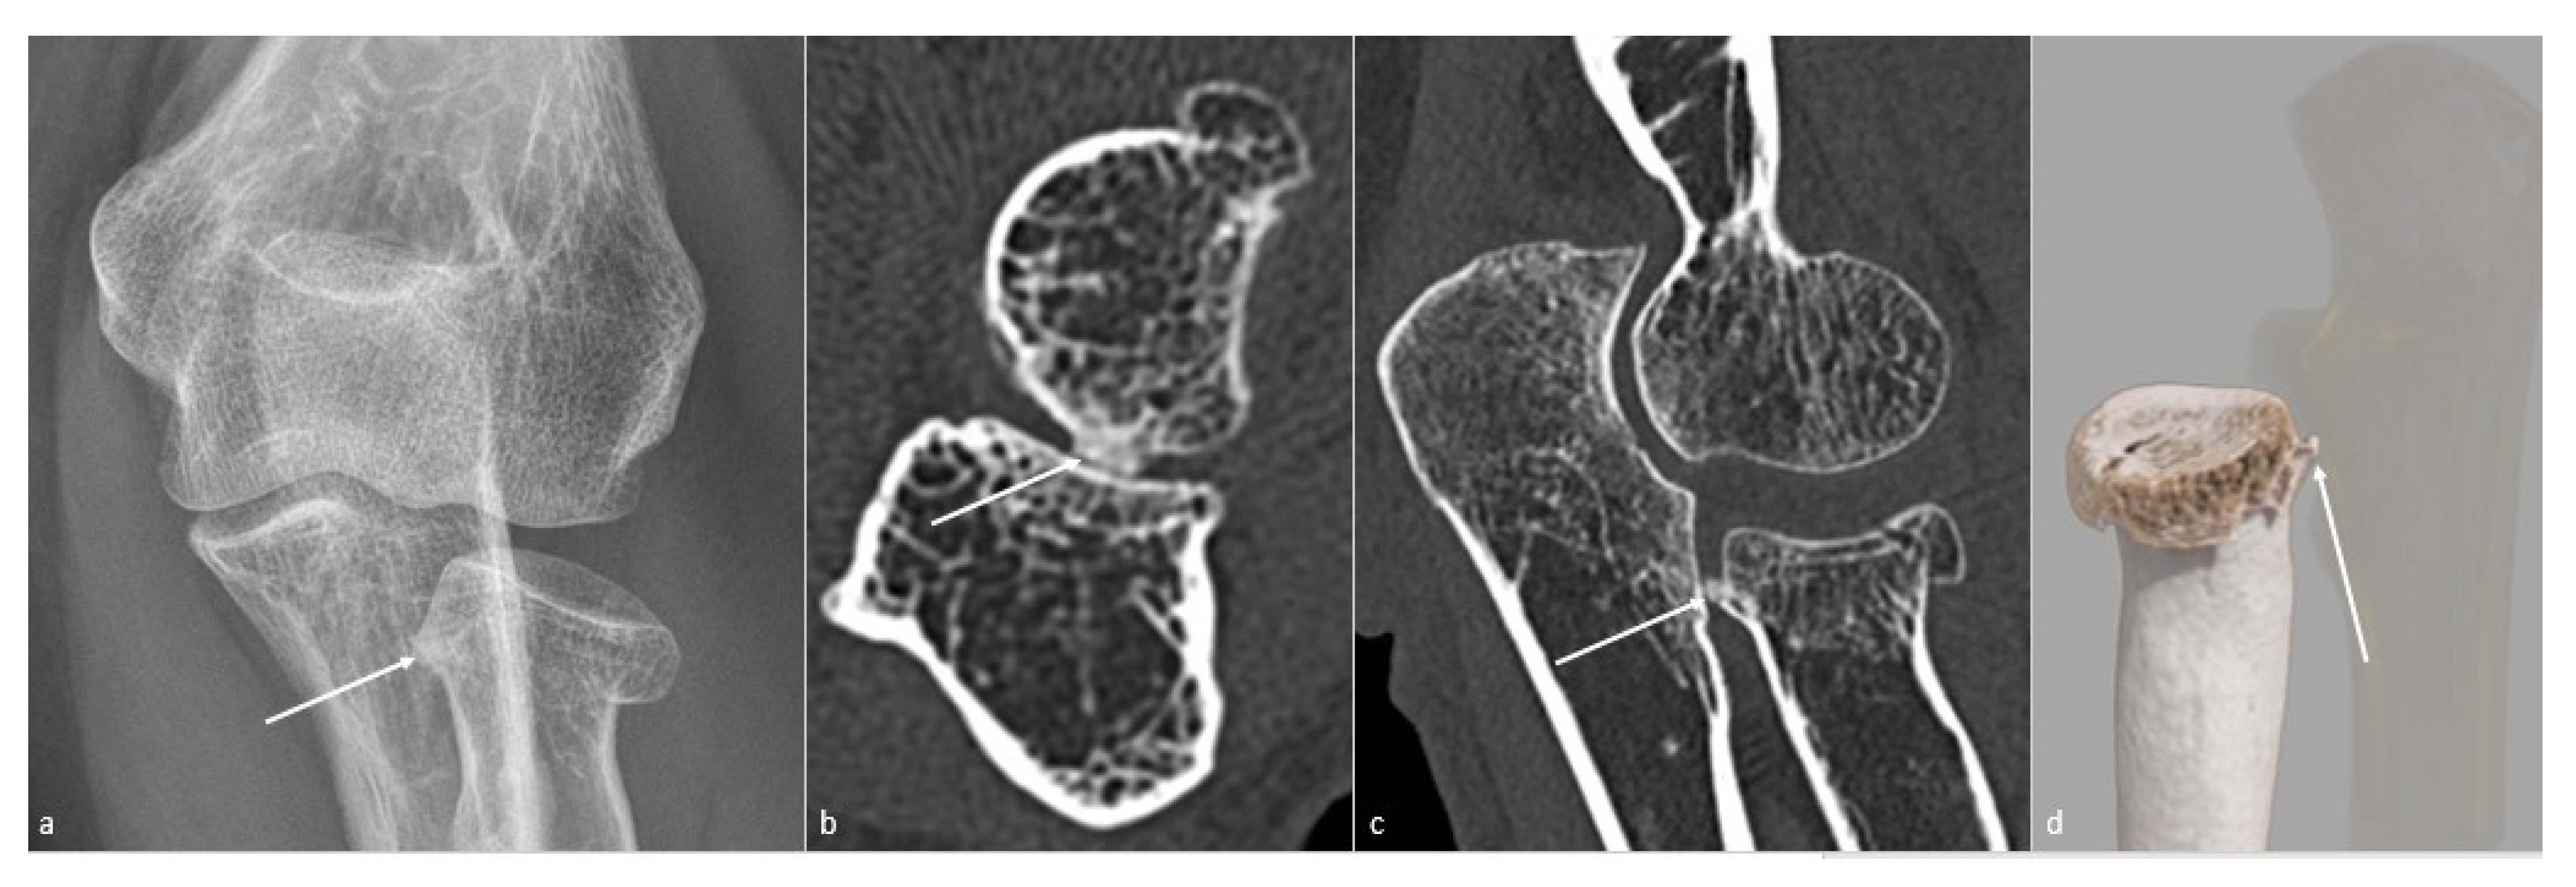

5.1. Conventional Radiographs

5.3. CT and CT Arthrography